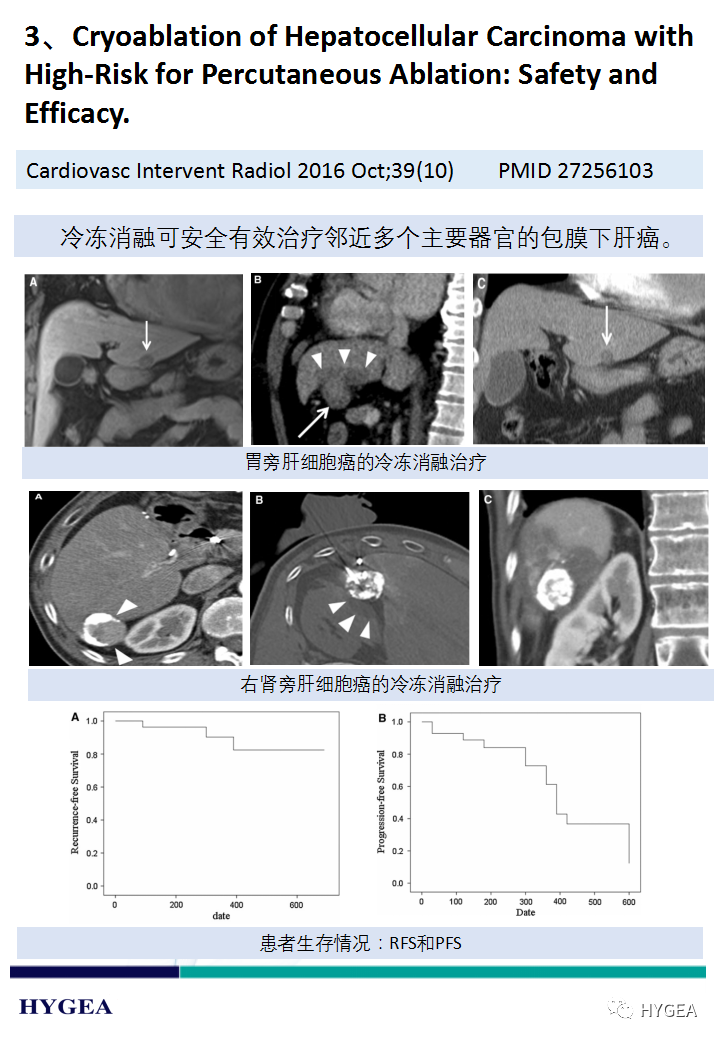

上一页:【海杰亚科研资讯】第189期——冷冻消融瘢痕疙瘩专题

下一页:【海杰亚科研资讯】第187期——冷冻消融肝癌专题